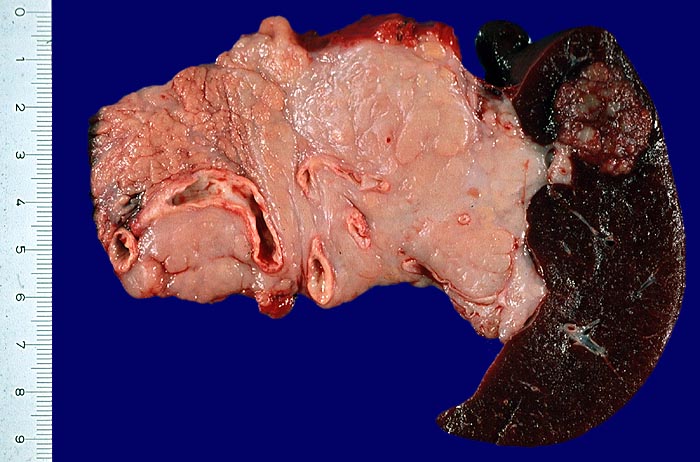

Makroskopie

Befund

Pathologischer Befund